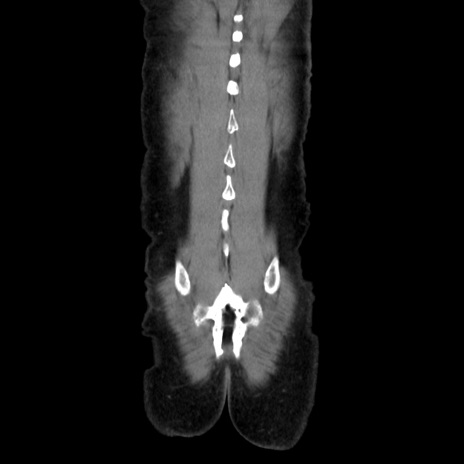

症例37(冠状断像)

【症例】40歳代 男性

【主訴】腹痛

【現病歴】4時間ほど前に電車に乗車中に臍部上より腹痛出現。徐々に増悪し起立困難となり、救急外来受診。生ものは数日食べていない。今朝お雑煮を食べた。

【身体所見】BT 36.8℃、BP 117/84mmHg、HR 91/min、SpO2 97%、苦悶様、腹部:臍上部広範囲圧痛あり、反跳痛±

【データ】WBC 8100、CRP 0.03